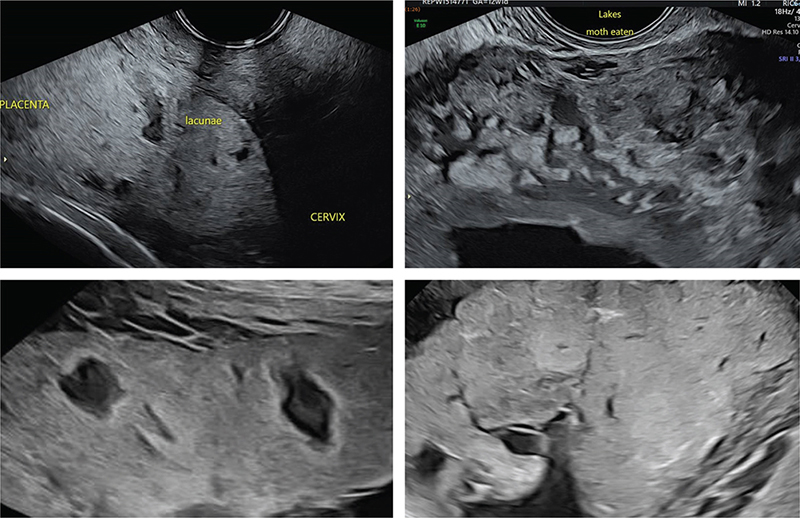

The most common ultrasound findings in the true positive cases were myometrial thinning (12/12 cases), loss of the placental basal plate (11/12 cases), loss of the sub-placental ‘clear zone’ (11/12 cases), and placental lacunae (10/12 cases) (Figs. 1 and 2). The presence of an exophytic mass was the only sign not observed in either true or false positive cases.

JOGM-5-331-F1.jpg

Fig. 1. Placenta increta. Left – focal placental lacunae, thin myometrium. Right – Subplacental hypervascularity, bridging vessels.